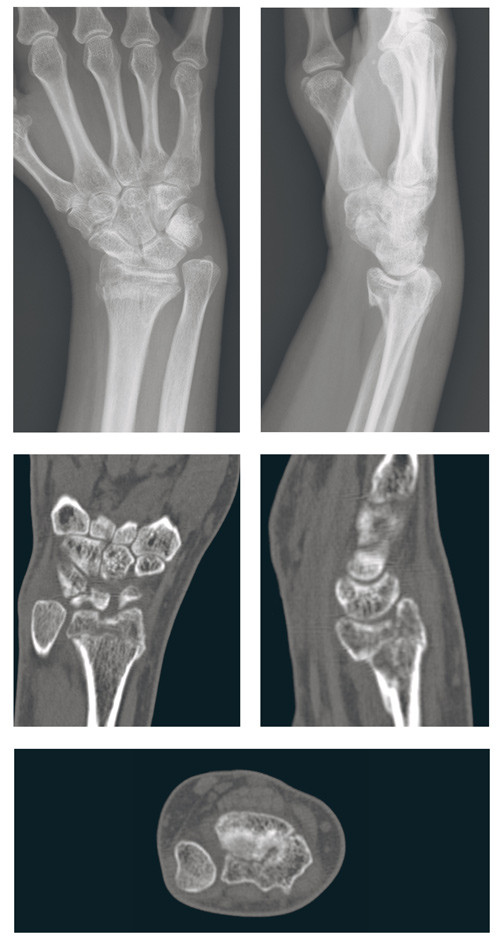

Til tross for økende vektlegging av behandling av distale radiusfrakturer er det stor variasjon i praksis. Ved mange sykehus tilstreber man differensiert behandling. Ved andre sykehus er tilbudet mer begrenset, både når det gjelder seleksjon av hvilke brudd som blir operert og valg av behandlingsmetode. Dette kan resultere i et dårligere resultat for noen pasienter enn det som kunne forventes ut fra dagens behandlingsmuligheter (fig 1). Disse forhold illustreres også i tall fra Norsk pasientskadeerstatning, som viser at distale radiusfrakturer er en av de hyppigste årsakene til klagesaker der pasienten har fått medhold (13). Det er derfor viktig å sikre pasienter med slike brudd optimal behandling. Formålet med denne artikkelen er å gjennomgå kunnskapsgrunnlaget for behandling av distale radiusfrakturer.